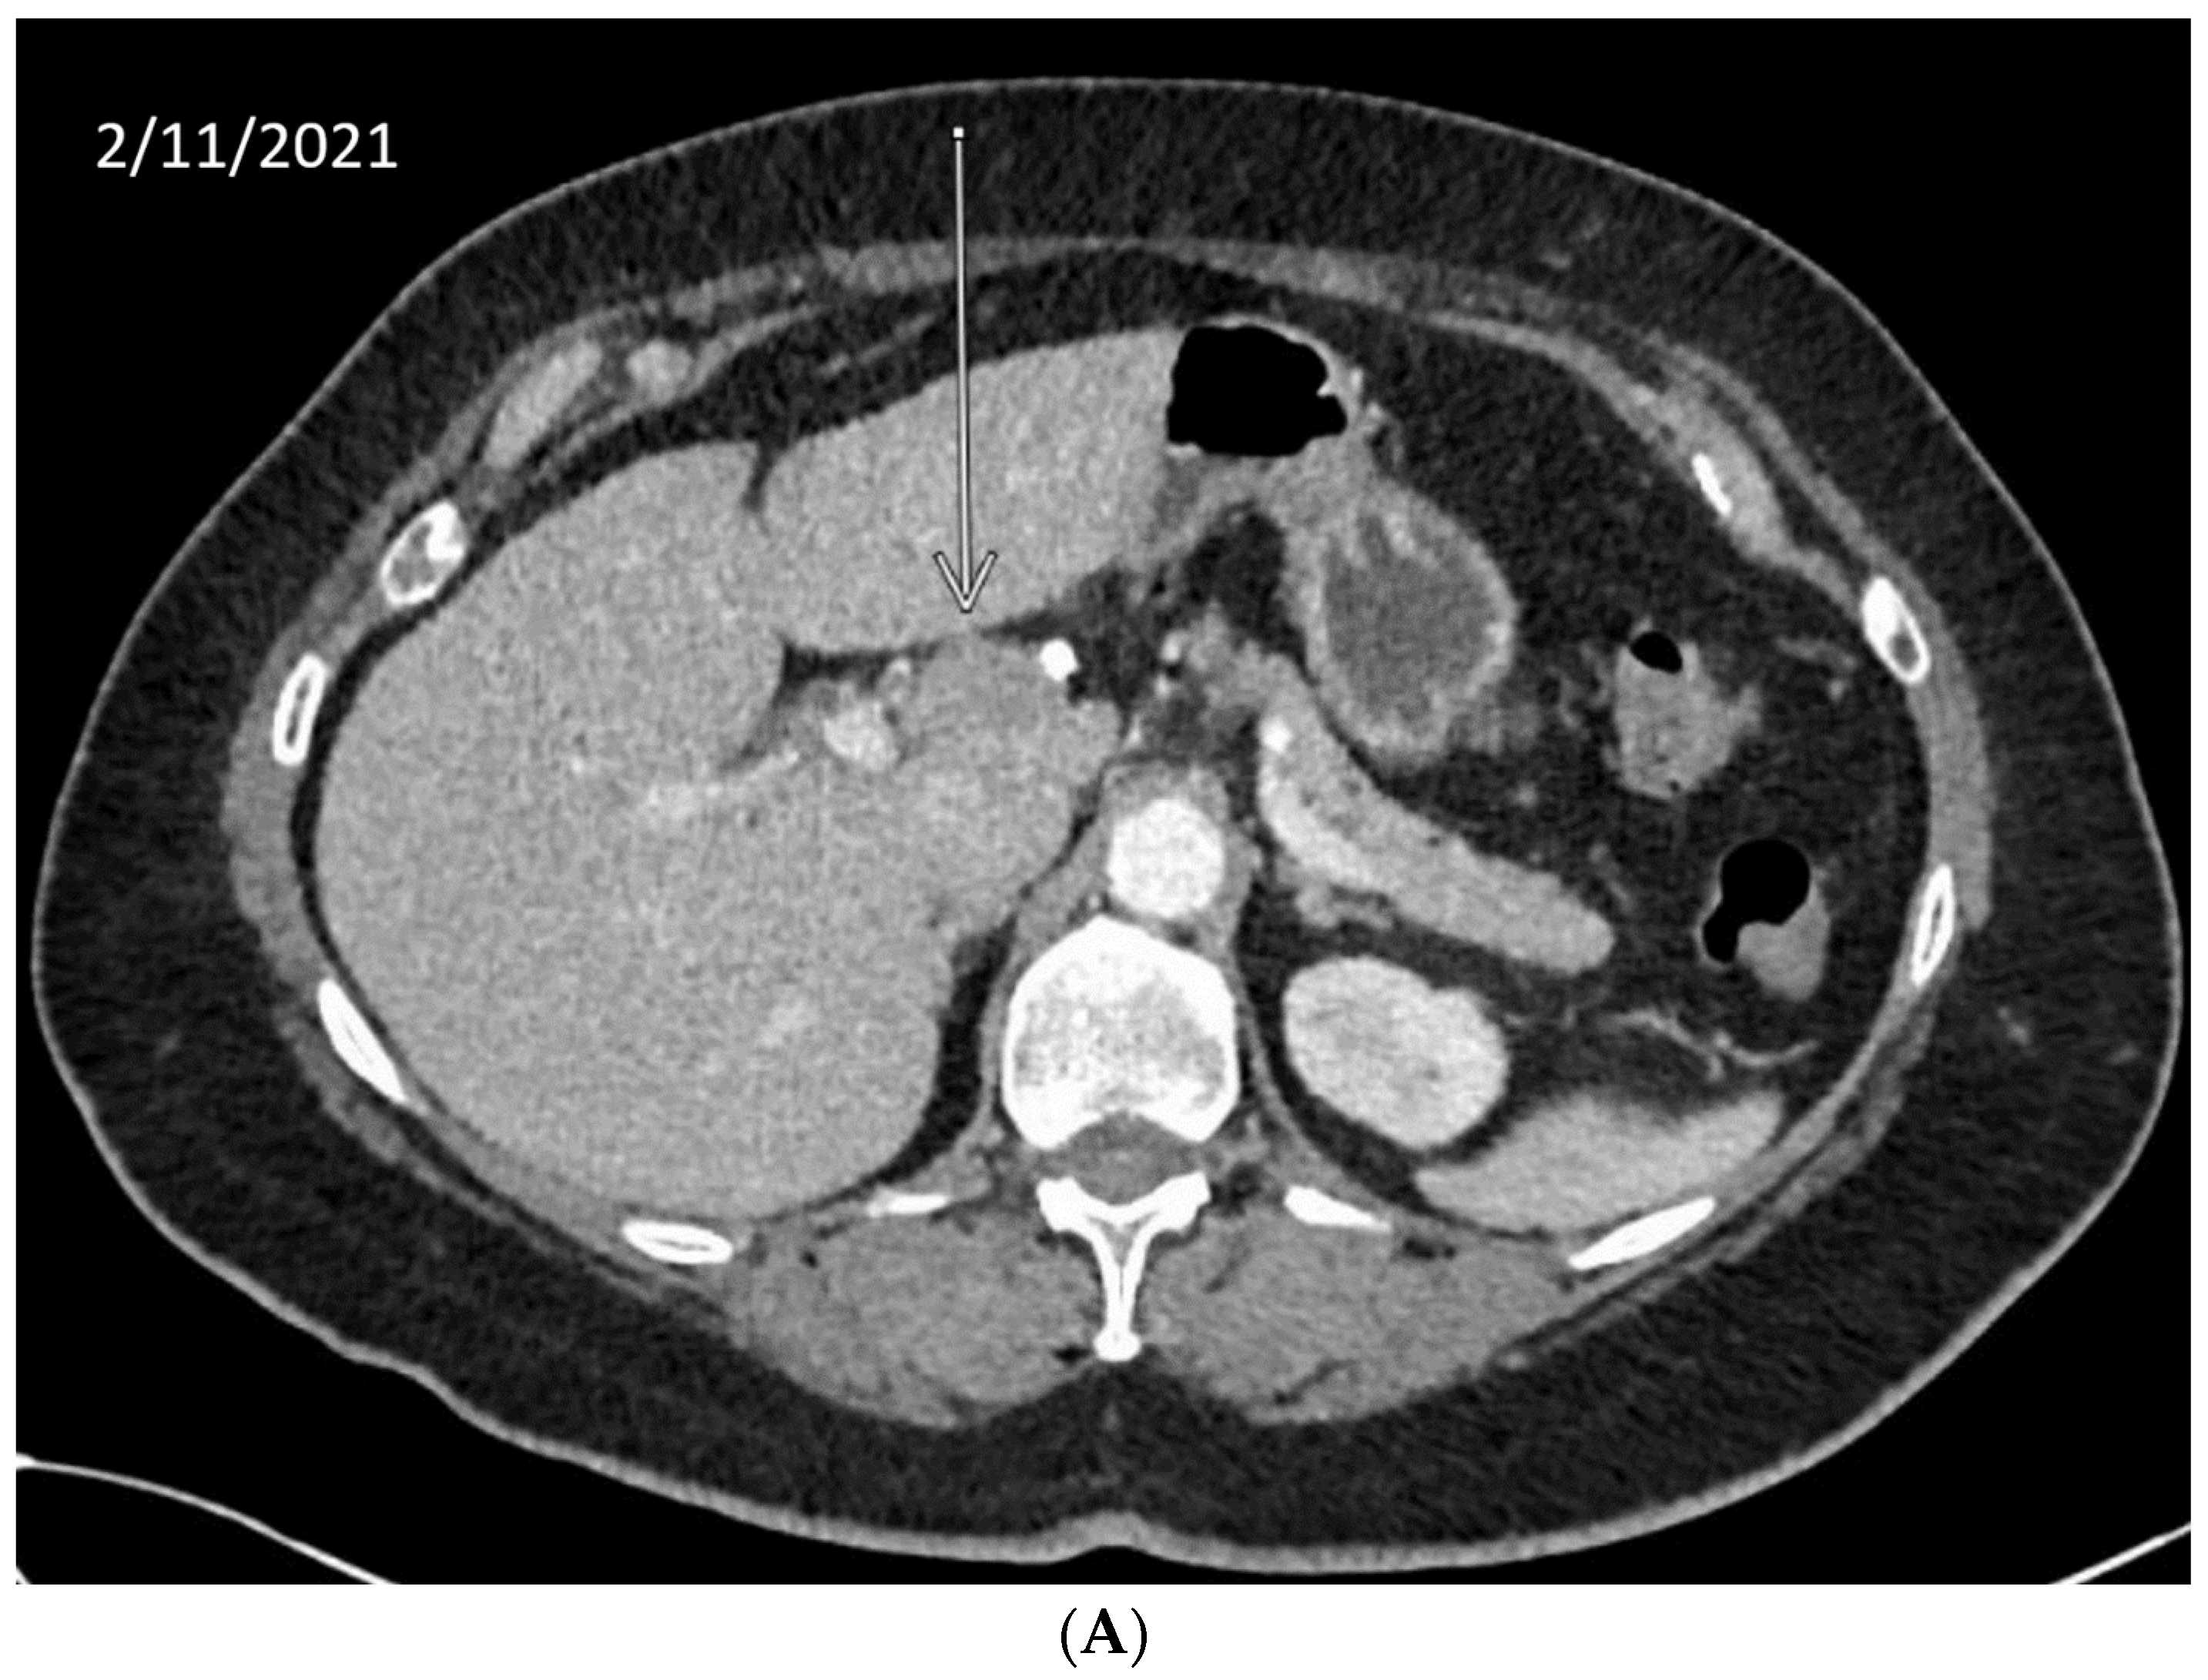

We describe our institutional experience of a 73-year-old woman presenting with metastatic BTC in March 2019. She was treated with GEMCIS between March and August 2019 and was switched to FOLFOX and fluorouracil maintenance therapy upon disease progression from August 2019 to December 2020, when she had further disease progression. She was then enrolled in our Phase II trial of olaparib plus pembrolizumab in relapsed/refractory advanced BTC in February 2021. As anticipated from her good response to platinum-based chemotherapy, the patient had an excellent partial response to PARPi in addition to ICI and a 65% decrease in index lesions (Figure 2). FoundationOne CDx comprehensive genomic profiling of the tumor showed a t(13;17) translocation with the chromosome 17 breakpoint identified in exon 4 of RAD51C (Figure 3A). This rearrangement had strong bi-directional evidence, with 237 supporting reads. Examination of chromosome 17 copy number data shows a copy number transition and accompanying LOH with a breakpoint at the RAD51C locus, suggesting likely loss of the second allele (Figure 3B). Genomic LOH, an orthogonal HRD signature validated as a companion diagnostic for rucaparib in ovarian cancer, was 11%, which is below the 16% threshold for gLOH-high status set in ovarian cancer. Biallelic inactivation of RAD51C has been associated with elevated gLOH [107]. However, the observed distribution of gLOH values varies by cancer type, and further study is needed to identify clinically relevant disease-specific thresholds [105]. The patient’s treatment was complicated by grade 3 immune hepatitis in June 2021; pembrolizumab has been held since then. She continued to respond to olaparib alone at the most recent clinical evaluation in February 2022.

Figure 2.

Time-lapsed CT images of a patient with intrahepatic CCA and RAD51C mutation (via t(13;17) translocation with the chromosome 17 breakpoint identified in intron 4 of RAD51C). She concurrently had a genomic loss of heterozygosity (gLOH) of 11%. The patient had an excellent response to treatment with PARPi and ICI and a 65% decrease in index lesion (shown by arrow). (A) CT from February 11, 2021. (B) CT from May 11, 2021. (C) CT from 7 February 2022.